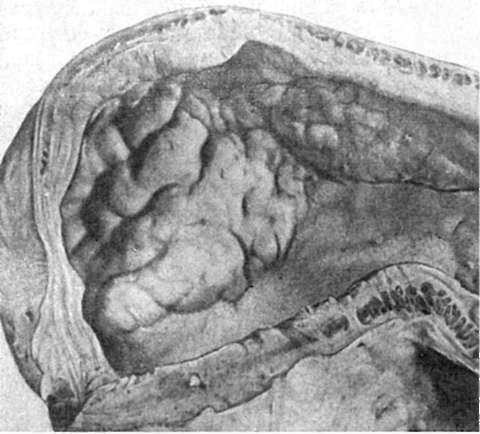

Рис. 94. Диффузный

рост злокачественной опухоли (рака) в стенке желудка

толще органа или на его поверхности. В одних случаях она диффузно пронизывает орган (рис. 94) и тогда границы ее не определяются, в других - расположена на поверхности органа (слизистой оболочки) в виде полипа (рис. 95). В компактных органах опухоль может выступать над поверхностью, прорастать и разрушать капсулу, аррозировать (разъедать) сосуды, вследствие чего возникает внутренее кровотечение. Она часто подвергается некрозу и изъязвляется (раковая язва). На разрезе опухоль имеет вид однородной, обычно бело-серой или серорозовой ткани, напоминая иногда рыбье мясо. Иногда ткань опухоли пестрая в связи с наличием в ней кровоизлияний, очагов некроза; опухоль может быть и волокнистого строения. В некоторых органах (например, в яичниках) опухоль имеет кистозное строение.